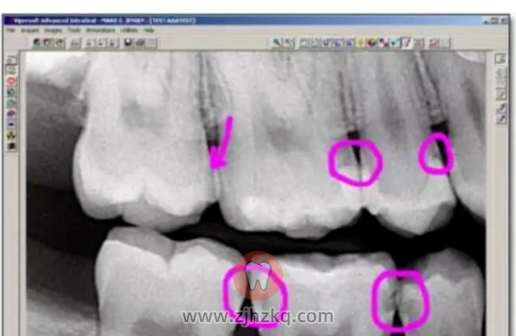

有这样疑虑的朋友们,来来来,让咱们先看看下面这个牙片,也许答案就出来了,圈的地方或多或少都有点龋齿,但是有些你并不能看见。

现在知道,我们徒眼看到的牙齿并非它的全貌了吧?不同的感觉下,其实隐藏着如此大的伤害。给您看牙的医生是没有透视眼的,而看牙不拍片就如同开车无驾照一样,所以看牙拍片不仅体现医生的严谨,更是对自己的负责。